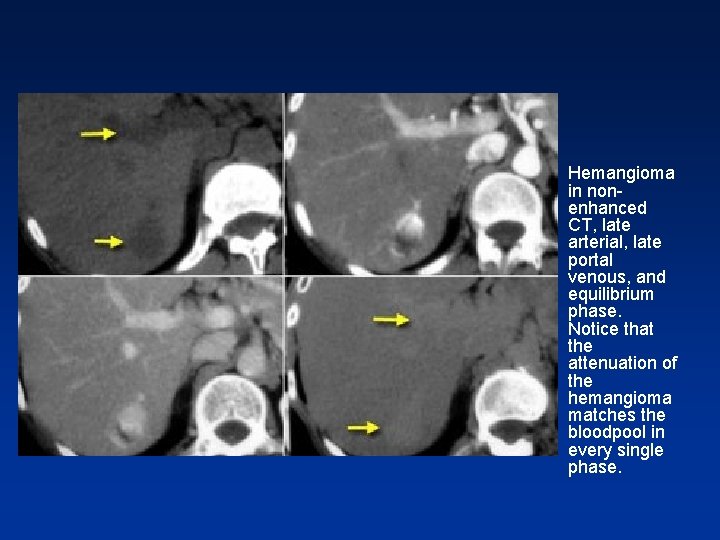

Blood pool and hemangioma • Normally when we look at lesions filling with contrast, the density of these lesions is always compared to the density of the liver parenchyma. • In hemangiomas, however you should not compare the density of the lesion to the liver but to the bloodpool

• This means that the areas of enhancement in a hemangioma should match the attenuation of the appropriate vessels { bloodpool } at all times. • So, in the arterial phase the enhancing parts of the lesion must have almost the same attenuation value as the enhancing aorta. • While in the portal phase, it must match the attenuation value of the portal vein. And so in venous or delayed phase.

• So, if it does not match the bloodpool in every single phase of contrast enhancement FOREGET the diagnosis of a hemangioma.

• Hemangioma in nonenhanced CT, late arterial, late portal venous, and equilibrium phase. Notice that the attenuation of the hemangioma matches the bloodpool in every single phase.

Hemangioma • Bloodpool and hemangioma • Normally when we look at lesions filling with contrast, the density of these lesions is always compared to the density of the liver parenchyma. • In hemangiomas, however you should not compare the density of the lesion to the liver but to the bloodpool

• So, if it does not match the bloodpool in every single phase of contrast enhancement , foreget the diagnosis of a hemangioma.